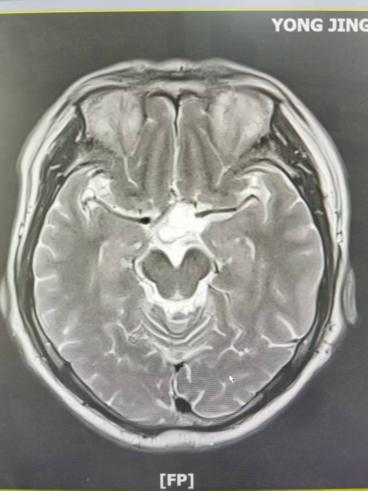

病例三:表皮样囊肿——掌握影像“金标准”

一例外伤患者,颅脑磁共振检查,显示患者小脑半球存在一特征性占位,在DWI序列上呈显著高信号——这一影像学表现正是表皮样囊肿(又称“珍珠瘤”)

表皮样囊肿虽为良性,但其沿蛛网膜下腔“见缝就长”的生长方式极具特点。通过对此病例的深入分析,孔令超对这一疾病的影像学“金标准”有了更深刻的认识,也进一步掌握了其与蛛网膜囊肿等相似病变的鉴别要点。这一病例的讨论,让团队对颅内囊性占位的鉴别诊断能力得到提升。